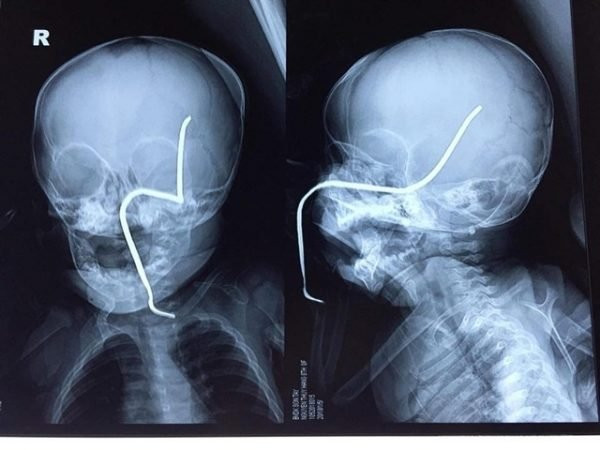

Phim chụp X-quang cho thấy thanh sắt xuyên qua má trái của bé H. (Ảnh: BVCC)

Nhập viện cấp cứu chiều 1/5, bé T.H (8 tháng tuổi, ở Sơn Tây, Hà Nội) luôn ở trong tình trạng kích động, quấy khóc. Bé bị một thanh sắt rỉ xuyên thẳng vào má trái, đâm vào hộp sọ.

Theo thông tin gia đình bé H. cung cấp, trong lúc đang mải chơi đùa, H. không may va phải chiếc máy cắt cỏ đang hoạt động. Chiếc máy làm bắn văng thanh sắt rỉ nằm ở dưới cỏ, cắm vào má trái. Thanh sắt xuyên thủng hộp sọ của H.

Ths.BS Hồ Trung Luân, khoa Ngoại Thần kinh, người trực tiếp phẫu thuật cho H. cho iết:" Ca mổ này có độ khó cao. Bởi thanh sắt đâm vào gò má trái, làm thủng sàn sọ, xuyên qua vùng não thái dương và vùng đỉnh sát các mạch máu lớn. Bên canh đó, thanh sắt rỉ, cũ, giòn, dễ gãy, lại nằm ở vị trí nhạy cảm nên nguy cơ chảy máu trong mổ lớn. Không chỉ vậy, H. còn có thể bị nhiễm trùng não, áp xe não".